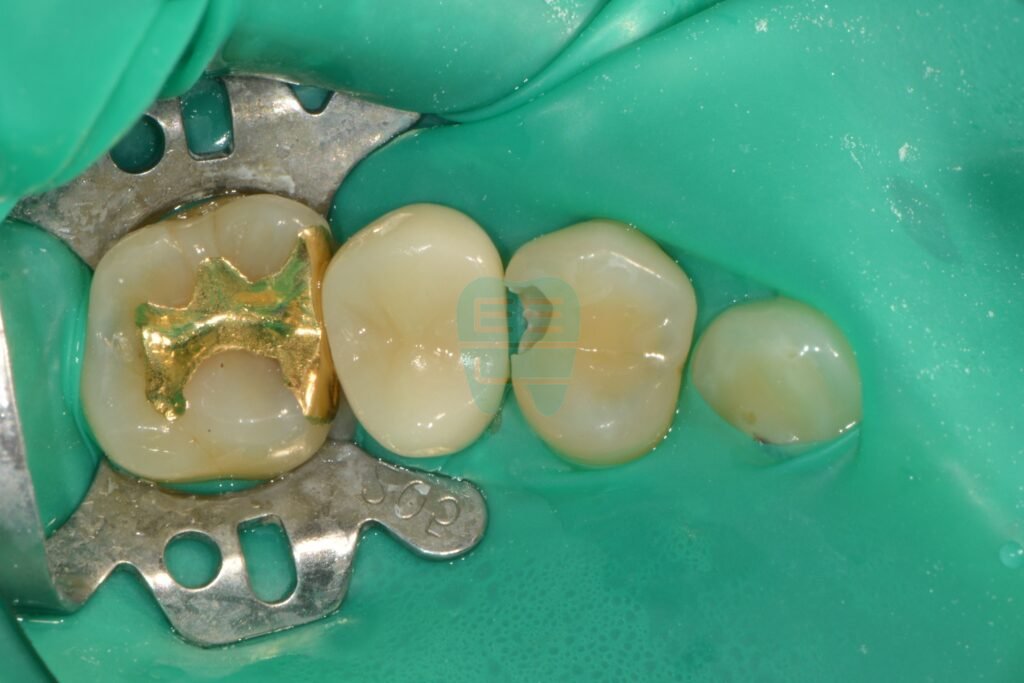

1. Rubber Dam Placement and Caries Confirmation

The first step in any caries treatment is thorough isolation. A rubber dam is placed to block moisture and bacteria, then the caries is exposed. What appeared to be a small opening turned out to have significant decay progressing beneath the surface.

After rubber dam isolation — caries removal in progress, deeper decay than expected

During caries removal